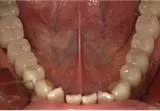

| 年齢/性別 | 50代女性 |

| 主訴 | 左下奥歯に痛みがある、全体的に治したい |

| 治療内容 | 全体的に歯周病やむし歯、根の治療を行い、仮歯を使用して咬合治療を実施。右下2本、左下1本の計3本を抜歯し、その後、右下に2本、左下に2本の計4本のインプラントを埋入しました。 |

| 治療期間 | 8か月 |

| 費用 | 2,106,500円税込 |

| リスク・副作用 | 炎症反応によって術後に腫れが生じることがあります。その程度は、手術の範囲や方法によって異なりますが、多くの場合、時間の経過とともに徐々に治まります。 ごく稀に、下顎奥歯の外科手術後に、唇や顎に痺れを感じることがあります。 |